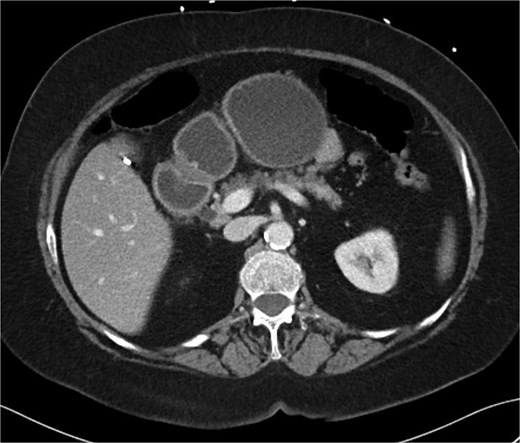

A 70-year-old woman with obesity, non-insulin-dependent diabetes, gastroesophageal reflux disease (GERD), cholecystectomy, and prior RYGB presented to the ED with acute chest and lower abdominal pain. The pain began 1 day earlier and initially responded to Ibuprofen, which she had been taking 4–6 times daily for musculoskeletal discomfort. Her pain worsened, radiating to her back, and was accompanied by belching and vomiting with dry heaving. She denied trauma or changes in bowel habits. Initial CT (Fig. 1) imaging showed a moderate hyperdense area around the duodenum, distension of the afferent limb and excluded stomach, and expected postoperative changes. She was admitted for conservative management. Four days later, a repeat CT (Fig. 2) was performed due to persistent symptoms, revealing free fluid in the intraperitoneal and retroperitoneal spaces, raising concern for duodenal perforation. She developed lethargy and diffuse abdominal tenderness and was taken to the operating room. Exploratory laparotomy with peritoneal washout, enterolysis, partial omentectomy was performed. It revealed two 1 cm posterolateral perforations of D3, which were repaired with an omental pedicle flap. The Roux limb was healthy, the jejunojejunostomy was dilated but patent, and the biliopancreatic limb was intact. Due to high vasopressor requirements, a temporary abdominal closure device was placed, and she was transferred to the surgical ICU. After stabilization, a second-look laparotomy was performed the next day to reinforce the duodenal closure, place a gastrostomy tube for drainage, and insert a J-tube for feeding (Figs 3 and 4). The abdominal wall was closed. On postoperative day 2, a CT with contrast showed extravasation from the duodenal repair site. Interventional radiology placed a transhepatic biliary drain to divert bile and support duodenal patch healing. Helicobacter pylori antigen was negative. Her condition improved, and she was started on an enteral and slow oral feeding regimen. However, at this juncture, the patient declined further treatment and requested comfort care measures.

Hospital Day 4 CT scan of the abdomen and pelvis A/P with oral and intravenous contrast demonstrating scattered pneumoperitoneum and free fluid by lateral duodenum.